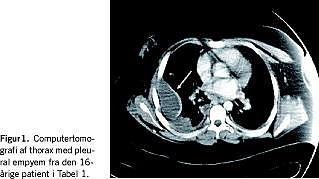

På Regionshospitalet Viborg var der i perioden 2004 til 2007 indlagt seks yngre patienter med strep A-antigentest-negativ Lemierres syndrom, hvilket svarer til halvandet tilfælde om året på hospitalet. Med et befolkningsgrundlag på ca. 250.000 vil det svare til 33 tilfælde om året i Danmark. De seks tilfælde er beskrevet i Tabel 1 og Figur 1.

Taksigelse: Vi takker Renè R. Jensen og Michel Laperriére, Billeddiagnostisk Afdeling, Regionshospitalet Viborg for hjælp til Figur 1.